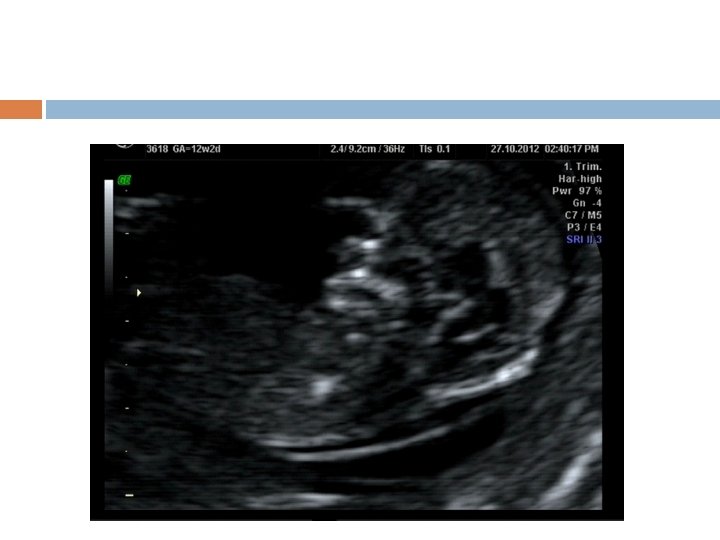

2 D USG

Nuchal Translucency

Protocol for measurement of nuchal translucency 11 to 13 weeks 6 days. CRL 45 and 84 mm. The magnification of the image should be such that the fetal head and thorax occupy the whole screen. A mid-sagittal view of the face The fetus should be in a neutral position, with the head in line with the spine Distinguish between fetal skin and amnion. The widest part of translucency must always be measured. Measurements should be taken with the inner border of the horizontal line of the callipers placed ON the line that defines the nuchal translucency thickness - the crossbar of the calliper should be such that it is hardly visible as it merges with the white line of the border, not in the nuchal fluid. Turn the gain down. A new approach for the measurement of NT which improves the accuracy of measurements, is with the use of a semi-automated technique.